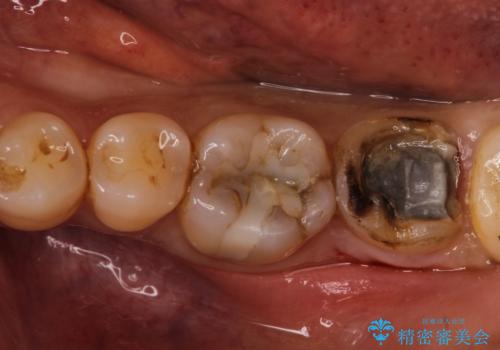

- 他院で入れた詰め物が壊れたとのことで来院された患者様です。

むし歯になっていたため、むし歯を除去し、セラミックインレーにて治療を行っております。

他の歯についても今後治療予定です。

色調は歯と自然な感じでなじみ大変満足されました。

レントゲンにて適合よく、残留セメントがないことを確認しています。